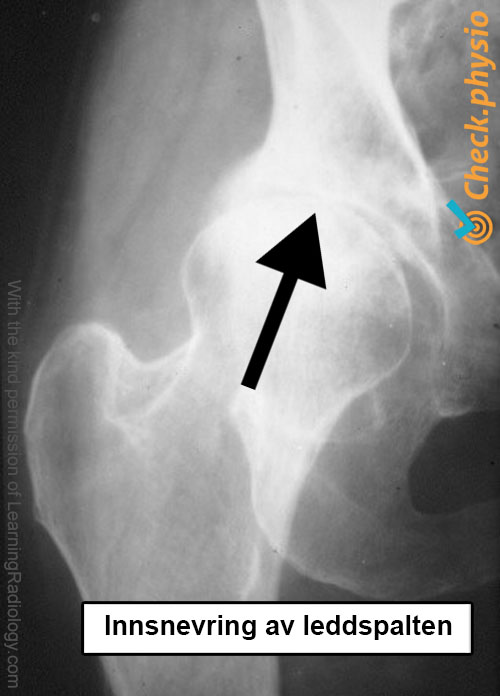

Den kliniske undersøkelsen og pasientens historie er som regel tilstrekkelig for å stille diagnosen. Røntgenbilder tas bare dersom det er tvil om diagnosen eller hvis en operasjon vurderes. Ved artrose viser røntgenbildet en innsnevring av leddspalten. I tillegg kan også andre konsekvenser av artrose være synlige, som dannelse av osteofytter.